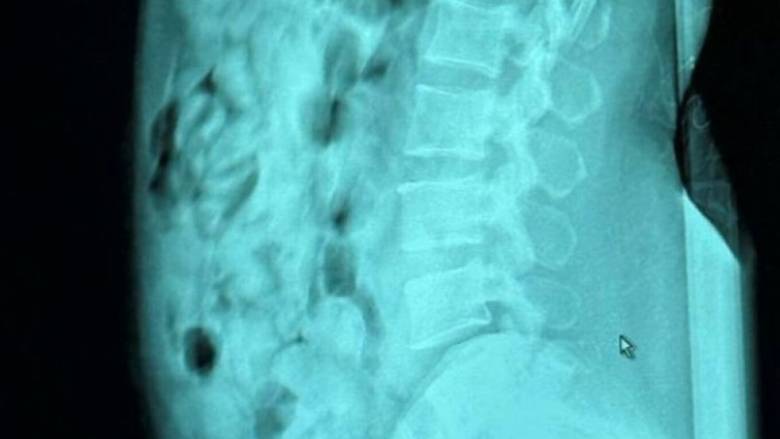

Ακτινολογικές εξετάσεις που πραγματοποιήθηκαν στο νοσοκομείο του Μπέργκαμο επιβεβαίωσαν ότι η γυναίκα είχε καταπιεί 120 σφαιρίδια, σχεδόν 1.393 γραμμαρίων ηρωίνης και τα οποία ήταν σφραγισμένα με κολλητική ταινία με προορισμό τη Σαρδηνία.

Η ακτινογραφία της 46χρονης που κατάπιε τις 120 αμπούλες ηρωίνης

Guardia di Finanza